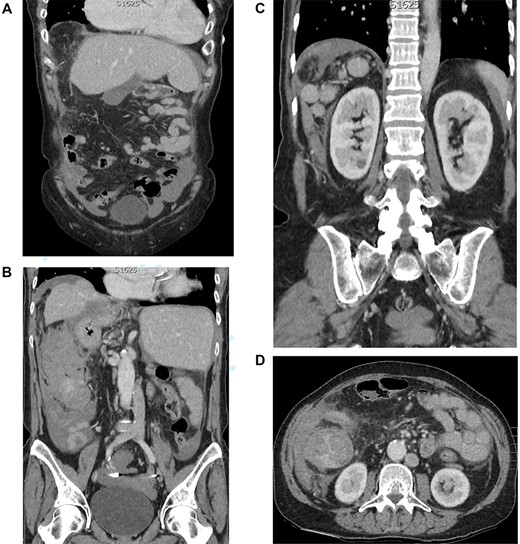

Figure 1 shows the plain film chest X-ray. Commuted tomography (CT) with intravenous contrast of the abdomen and pelvis confirmed SI totalis (Fig. 2). Polysplenia with five splenunculi, a lobulated 130 mm mass with heterogenous contrast enhancement and free fluid were noted in the right upper quadrant on CT (Fig. 2). Upon return from CT the patient became tachycardiac and hypotensive to 62/44 mmHg for which she was fluid responsive to 2 L IV crystalloid. Repeat haemoglobin was now 109 with a lactate of 0.9 and no significant acid–base disturbance. Group and Save, IV 10 mg vitamin K and 2300 IU of prothrombinex-VF were ordered, and the general surgical team was consulted urgently.

(A) CT coronal cross section demonstrating a left-sided liver and gallbladder. (B) CT coronal cross section demonstrating a right-sided stomach and abdominal aorta, left-sided inferior vena cava and the heterogenous lobulated mass with free fluid. (C) CT coronal cross section demonstrating the five splenunculi. (D) CT axial cross section demonstrating the 130 mm heterogenous lobulated mass in the right abdomen